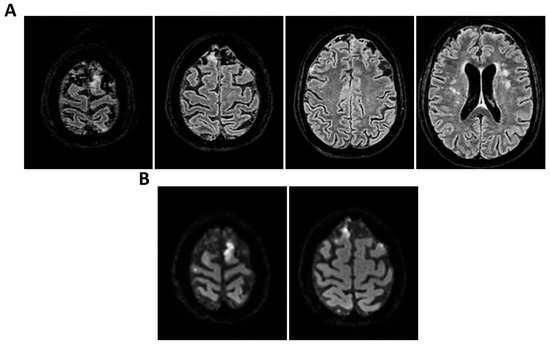

Background: Meningoencephalitis is a complex inflammatory condition of the CNS that can result in significant morbidity and mortality in critically ill adults. Accurate and timely neuromonitoring is essential for guiding management and improving outcomes. This study aimed to descriptively evaluate the prognostic value of early TCCD monitoring, particularly the pulsatility index, and its integration with conventional and perfusion MRI in patients with meningoencephalitis. Methods: We present an observational, retrospective, cohort study involving ten adult patients (median age 56 years, IQR 45.5–68.5; mean 55.9, range 35–76) with neurological syndromes caused by suspected or confirmed infectious meningoencephalitis. Etiologies included bacterial meningitis/meningoencephalitis (50%), viral meningoencephalitis (10%), neurotoxoplasmosis (10%), progressive multifocal leukoencephalopathy (10%), and undetermined origin (20%). Patients underwent TCCD and MRI within 24 h. In five cases, standard MRI sequences were acquired, while in the remaining five, perfusion imaging was performed using Arterial Spin Labelling (ASL). A favorable outcome was defined as survival with neurological recovery (Glasgow Outcome Scale > 5) at ICU discharge. Results: TCCD-derived PI provided valuable information on cerebral hemodynamics. PI values ≤ 1.25 were associated with favorable clinical outcomes and symmetrical MRI findings. Conversely, PI > 1.25 correlated with poor prognosis and often preceded MRI-detectable structural damage. When combined with ASL, PI mirrored the detected perfusion asymmetries and was associated with poor prognosis in fatal cases. Conclusions: Bedside TCCD can offer real-time assessment of cerebrovascular dynamics and, when integrated with conventional and ASL MRI, could enhance the understanding of pathophysiological processes in meningoencephalitis, supporting timely and informed decisions in neurocritical care.